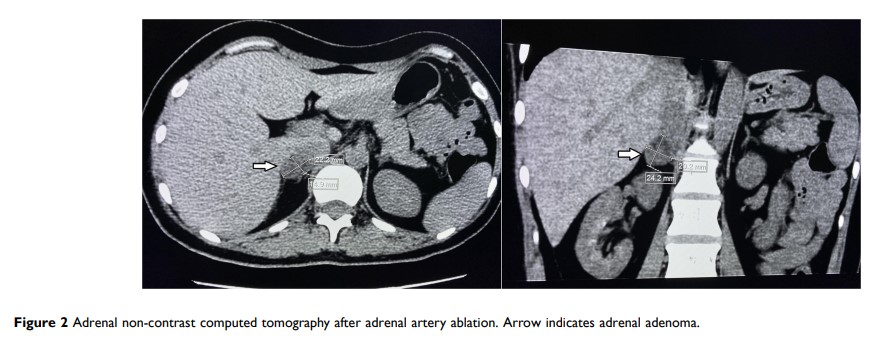

根据肾上腺静脉取血,采用肾上腺动脉消融术治疗皮质醇增多症:一种潜在的治疗策略